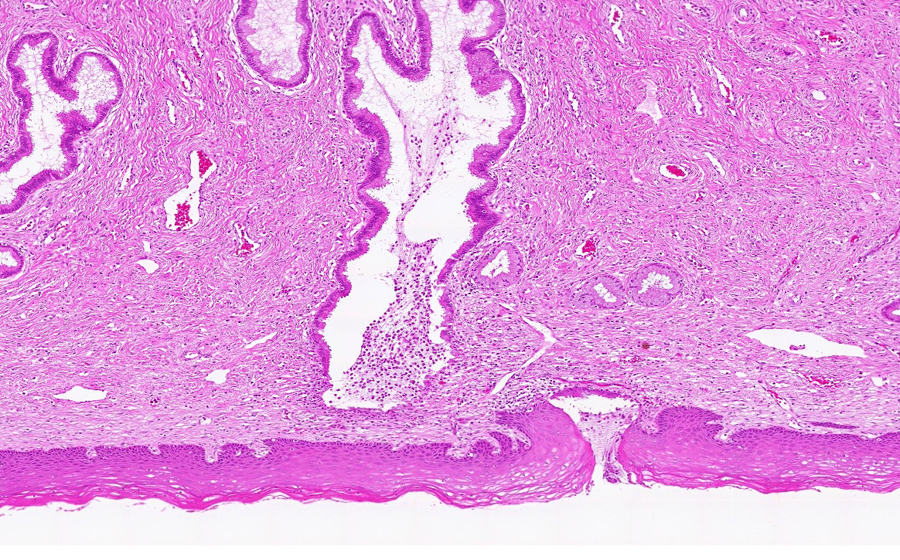

Slide 3: Chronic cervicitis and metaplasia

Histologic section of cervix from a patient with chronic cervicitis (click here to review normal tissue)

Image 1 - 3.1X

Slide 3 - Image 1